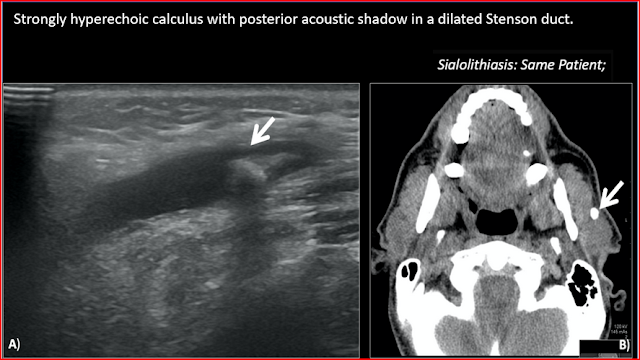

- SIALOLITHIASIS:

The clinical history is usually of recurrent pain and swelling of the affected gland, particularly related to meals.

US is an important tool as a first-line assessment of ductal ectasia and lithiasis. Besides calculi, imaging may show associated features, such as ductal ectasia, heterogeneous gland parenchyma and possible abscesses. It is important to determinate the location of the stone (intraductal or intraglandular). However, small calculi (inferior to 2-3 mm) may not be detected. CT provides a good detection of calculi and assessment of adjacent gland.